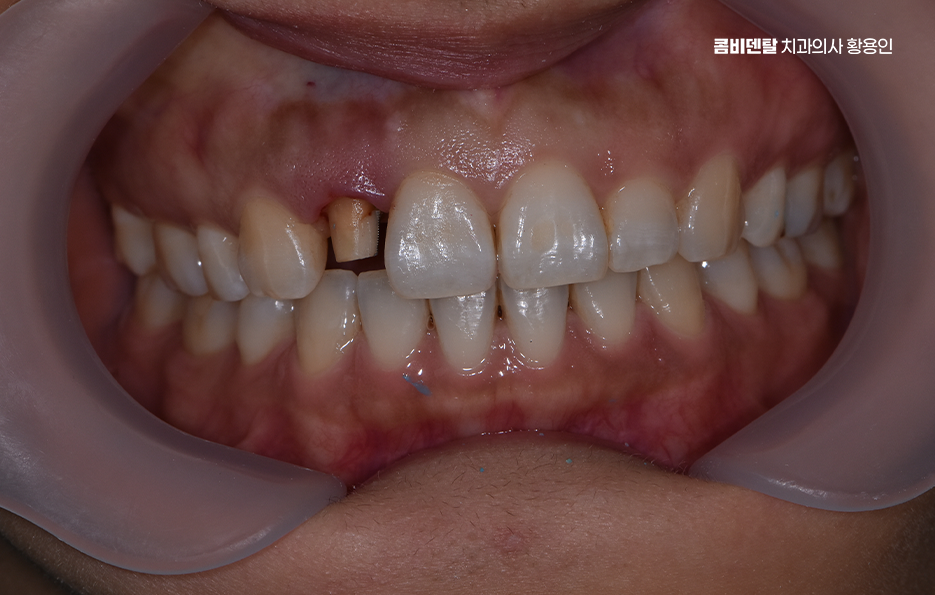

앞니 올세라믹 치료는 과정을 살펴보면 우선 정확한 진단이 필요한데 현재 치아 상태가 올세라믹으로 치료 가능한지, 신경치료가 필요한지 여부와 치아 삭제량은 어느 정도로 해야 하는지 등을 평가하며 특히 앞니는 단순히 하나의 치아만 보지 않고, 양옆 치아와의 길이, 색상, 형태, 그리고 웃을 때 보이는 ‘스마일라인’까지 함께 고려해야 하기 때문에, 치료를 하기 전에 충분한 상담과 앞니 올세라믹의 특징에 대한 올바른 이해가 필요한 거예요

다음으로 올세라믹은 금속이 없기 때문에 두께가 일정 이상 확보돼야 강도와 자연스러움을 유지할 수 있다는 특징이 있어서 치아를 일정량 이상 깎아내야 하는데, 이때 너무 과도하게 삭제하면 치아 신경이 노출될 위험이 있고, 너무 적게 삭제하면 올세라믹 크라운이 두껍거나 부자연스러워질 수 있어서 삭제 깊이와 방향을 정밀하게 조절하는 게 중요하며 만약 이미 치아가 많이 손상되어 신경치료가 필요한 경우라면 이 단계에서 먼저 근관치료를 진행하고, 보철물 준비를 하게 되는데 인상은 기존에 석고로 뜨던 방식 외에 요즘은 디지털 구강 스캐너를 이용해서 3D 데이터로 정밀하게 채득할 수도 있으며 이렇게 하면 환자도 편하고, 보철물의 정밀도도 더 높아질 수 있어요